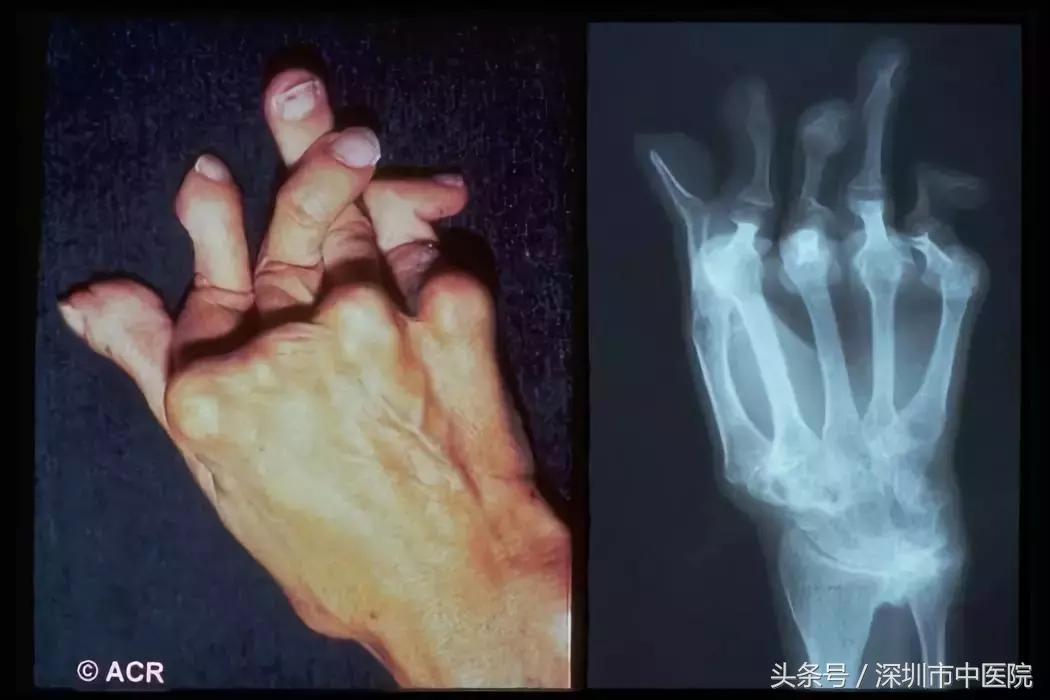

类风湿关节炎(RA)是一种病因不明的,以侵犯关节滑膜为主要特征的慢性、炎症性、系统性结缔组织病,属于自身免疫性疾病。女性是类风湿性关节炎的重灾区,发病率为男性的2~3倍。可发生于任何年龄,高发年龄为40~60岁。

表现为对称性、持续性关节红、肿、热、痛和功能障碍,主要侵及周围小关节和大关节,以近端指间关节、掌指关节和腕关节最常见,其它依次为足、肘、肩、踝、膝、颈、颞颌及髋关节等,后期可发展为关节畸形,乃至残废。